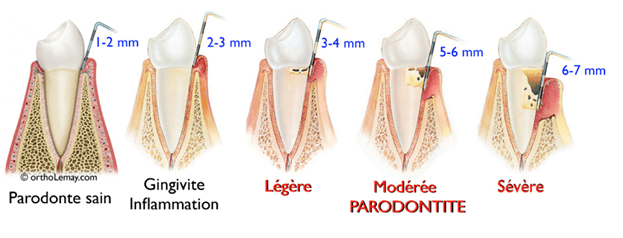

Lors de la consultation, votre Chirurgien-Dentiste passe en revue l’historique médical et dentaire. Il examine ensuite les gencives et les dents à la recherche de signes d’une parodontite. Il prend alors des mesures au niveau de la gencive avec une fine sonde pour déterminer si un espace est présent entre la dent et la gencive sous forme de poche appelées aussi « poches parodontales ». Des radiographies peuvent être proposées pour observer le niveau osseux sous les gencives. Nous vous proposerons ensuite un traitement adapté.